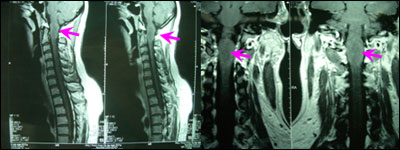

延颈交界髓内肿瘤

男性,22岁,双上肢无力渐延至双下肢20天,伴呼吸困难。查体:双上肢近端肌力3级、远端4级,双下肢近端4级、远端5级,深感觉障碍,双侧病理征阳性。

术前图片:

术后病理结果为星形细胞瘤。术后患者没有新出现的神经功能缺失,肌力有所恢复,一年后本体感觉亦有所恢复。

专家评点:上一世纪八十年代髓内肿瘤是手术禁忌,九十年代因显微神经外科的开展,髓内肿瘤才得以很好的治疗。颈髓内肿瘤致命的威胁是呼吸肌麻痹所致的呼吸困难、停止,而且病程较短,为限期手术。该手术在严格后正中切开脊髓后将大部分肿瘤组织切除,良好内减压后,明确肿瘤性质,为术后的辅助治疗措施奠定基础。